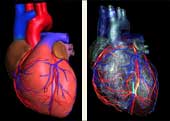

Koronarna CT angiografija

Kardiovaskularne bolesti su ubica broj jedan u današnjem svijetu i odnose svake godine više života nego sve maligne bolesti zajedno. Koronarna bolest je najčešće uzrokovana aterosklerozom (stvaranjem plakova u zidu krvnih žila uzrokojući njihvo suženje). Donedavno, nije postojao neinvazivni način da se direktno analiziraju koronarne arterije na prisustvo aterosklerotskih promjena. Razvoj tehnologije višeslojnog CT-a (MSCT/MDCT) omogućio je detaljno trodimenzionalno prikazivanje kucajućeg srca u toku jednog zadržavanja daha. U našem dijagnostičkom centru nudimo ovu tehniku pregleda koronarnih arterija, na multi-slice aparatu, s najmodernijim softverom i minimalnom dozom zračenja.

Šta je CT koronarografija?

To je metoda prikaza malih arterija koje hrane srčani mišić, upotrebom CT skenera, koji prikazuje protok krvi u koronarnim arterijama i kompjuterskog softvera da bi se dobio odgovarajući trodimenzionalni prikaz. CT angiografija je neinvazivni način da se prikažu zidovi koronarnih arterija I nadju eventualni aterosklerotski plakovi, što pomaže liječniku u odredjivanju rizika srčanog udara.